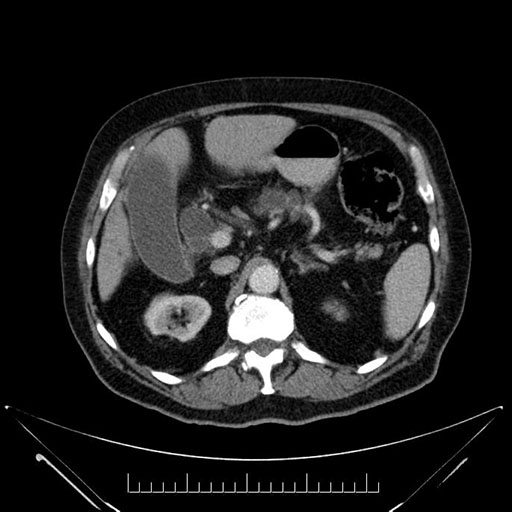

Whipple (pancreaticoduodenectomy) [case 7]

Imaging Analysis

Look through the patient's CT scan to identify any areas of concern for the necessary procedure.

Based on your CT findings, which issue(s) would give reason for "planned slowing down moment(s)" in this case?

Considering a standard Whipple procedure, what step(s) of the operation would you do differently in this case?